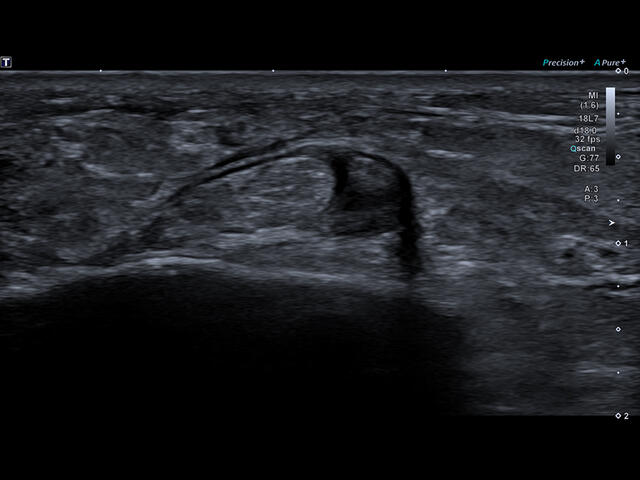

Уровень сосудистой визуализации SMI в сочетании с высокой частотой кадров повышает диагностическую достоверность при оценке поражений, кист и опухолей.

SMI с цветовой кодировкой позволяет одновременно отображать информацию о потоках и оттенках серого с высокой временной и пространственной информацией.